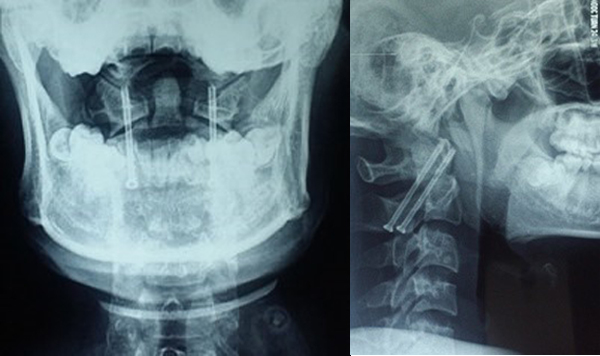

Đánh giá kết quả sau mổ 1 tháng, tất cả bệnh nhân có chỉ số giảm chức năng cột sống cổ NDI ở mức độ không ảnh hưởng, VAS cải thiện rõ trung bình 1 ± 0,816 (0-2), vận động cột sống cổ bình thường với vít trực tiếp mỏm nha, hạn chế nhẹ với vít qua khớp. Chụp X quang các tư thế, chụp cắt lớp vi tính cột sống cổ cho thấy không có di lệch vị trí đặt vít, không mất vững đội – trục.

Kỹ thuật vít trực tiếp mỏm nha và vít qua khớp C1-C2 điều trị gãy mỏm nha type 2 bước đầu cho kết quả hồi phục chức năng cột sống cổ tốt, giảm đau rõ, duy trì được tầm vận động cột sống cổ đặc biệt là kỹ thuật vít mỏm nha đã giữ nguyên được giải phẫu của khớp cột sống cổ cao.